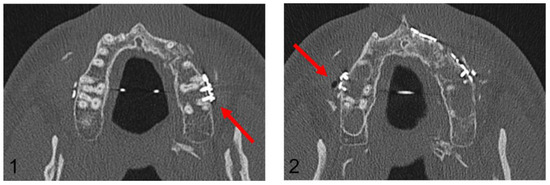

Figure 6.

Post-operative orthopantomogram after the conventional maxillary positioning, showing the projections of three osteosynthesis screws with the dental roots of the teeth 16 and 17 and the projections of four osteosynthesis screws with the dental roots of the teeth 26 and 27 (red arrows).

Figure 7.

Axial plane of post-operative CT scan. Image (1) shows an injury of the mesiobuccal tooth root of tooth 27, while in image (2), no root injury in the right maxillary molars is detected (red arrows).

In the Maxilla Conventional cohort, 94 radiological projections of osteosynthesis screws with the dental roots were detected in the post-operative OPG. In contrast, post-operative CT imaging detected only 10 dental root injuries. In the Maxilla PSI cohort, 64 radiological projections were detected; however, no dental root injury could be detected in post-operative CT imaging. In the mandible, a total of 106 projections in the premolar and molar region were recorded in the post-operative OPG, but only 12 root lesions were detected in post-operative CT scan.